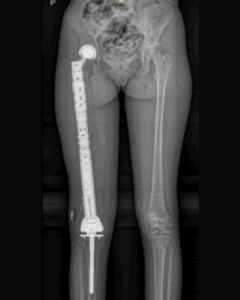

Rostoucí endoprotézaLéčba nádorů kostí a kloubů u dětí patří mezi nejnáročnější výzvy moderní ortopedie. Po odstranění nádoru je nutné nahradit chybějící část kosti tak, aby se zachovala funkce končetiny a umožnil další růst dítěte. Jednou z možností jsou tzv. rostoucí endoprotézy – speciální implantáty, které lze v průběhu času prodlužovat bez nutnosti opakovaných operací.

Endoprotézy umožňují náhradu rozsáhlých částí kostí a kloubů, například stehenní nebo holenní kosti, kyčle či kolene.

• kompletní náhrada stehenní kosti včetně kyčle a kolene,